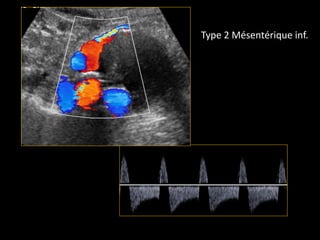

ENDOFUITE TYPE 2

TYPE 2TYPE 2

ReperfusionReperfusion parpar

circulation rcirculation réétrogradetrograde

(branche(s) de l(branche(s) de l’’aorteaorte

native)native)

ArtArtèère lombaire,re lombaire,

mméésentsentéérique infrique inféérieure,rieure,

iliaque interneiliaque interne

Type 2 Mésentérique inf.

ENDOFUITE TYPE 2 TYPE2TYPE 2 ReperfusionReperfusion parpar circulation rcirculation réétrogradetrograde (branche(s) de l(branche(s) de l’’aorteaorte native)native) ArtArtèère lombaire,re lombaire, mméésentsentéérique infrique inféérieure,rieure, iliaque interneiliaque interne Type 2 Mésentérique inf.